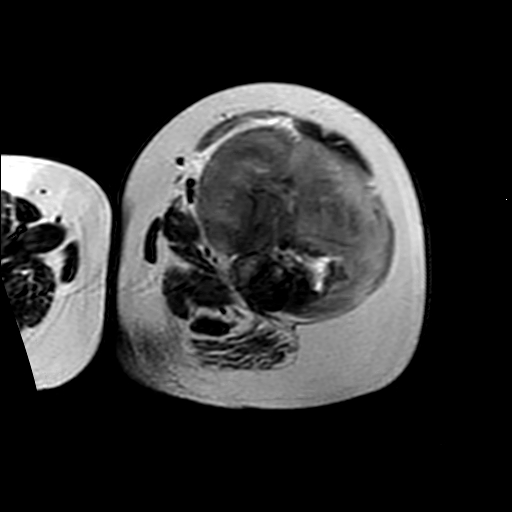

左侧大腿外伤10余年,当时情况不清,发现左侧大腿肿胀7年余,而后又有多次外伤史,近1年来出现疼痛,减重半年。查体:左侧大腿肿胀明显,皮温、肤色正常。

增强

软组织肿块,股骨破坏,增强不均匀强化-----支持恶性肿瘤